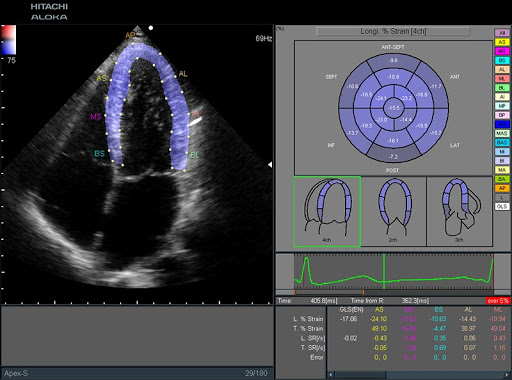

Сканер компактный и экономичный. Его легко настроить под конкретного врача и переместить внутри клиники. Аппарат позволяет проводить множество расширенных исследований, включая виртуальную сонография в реальном времени, эластографию тканей в реальном времени, 2D-Tissue Tracking (количественная оценка движения и утолщения сердечной мышцы).

- Широкий кардиопакет